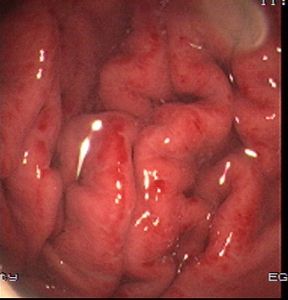

急性腸胃炎的症狀主要表現為噁心、嘔吐、腹痛、腹瀉;發熱等,嚴重者可致脫水、電解質紊亂、休克等。病人多表現為噁心、嘔吐在先;繼以腹瀉,每日3—5次甚至數十日不等,大便多呈水樣,深黃色或帶綠色,惡臭,可伴有腹部絞痛、發熱、全身酸痛等症狀。治療

(二)急性腸胃炎的臨床表現家庭生活中一般在暴飲暴食或食用了污染食物、服對胃有刺激的藥後數小時至24小時發病。主要為:

診斷要點急性腸胃炎在臨床上的主要表現為噁心、嘔吐、腹痛、腹瀉、發熱等,嚴重者可致脫水、電解質紊亂、休克等。病人多表現為噁心、嘔吐在先,繼以腹瀉,每日3—5次甚至數十次不等,大便多呈水樣,深黃色或帶綠色,惡臭,可伴有腹部絞痛、發熱、全身酸痛等症狀。急性症狀,藥物治療陳主任認為,一旦得了急性腸胃炎,應該儘量臥床休息,並且口服葡萄糖、電解質液以補充體液的丟失。

(2)起病急,噁心、嘔吐頻繁,劇烈腹痛,頻繁腹瀉,多為水樣便,可含有未消化食物,少量粘液,甚至血液等。